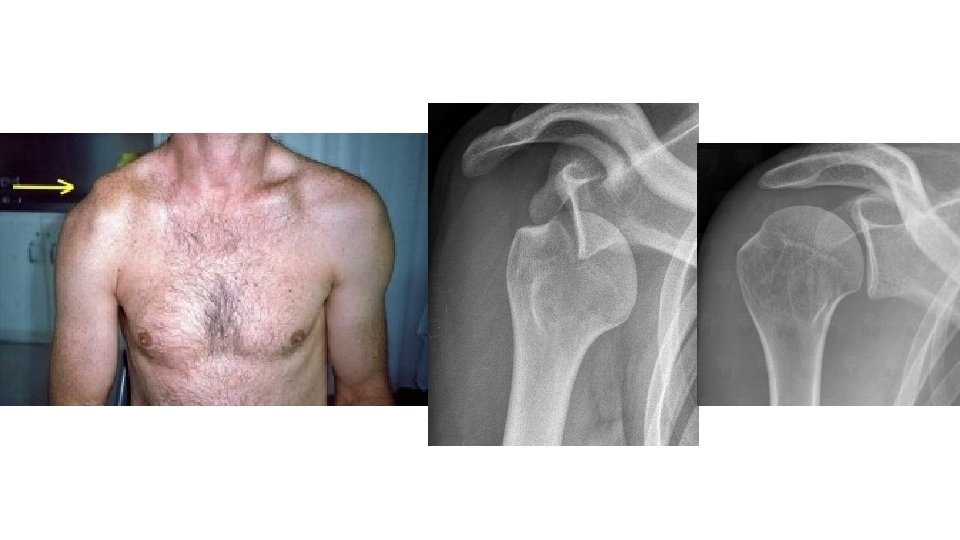

Luxation • La luxation est une déchirure des ligaments (donc entorse) avec en plus l'articulation déboitée. C'est la perte des rapports articulaires normaux • Il s’agit toujours d’une urgence chirurgicale

Clinique • Déformation • Douleur • Impotence totale

Gestes • Ablation bagues et bijoux – A JEUN • Examen NEURO-VASCULAIRE et CUTANE

Gestes • Ablation bagues et bijoux – A JEUN • Examen NEURO-VASCULAIRE et CUTANE = recherche signes de gravité immédiate (ouverture/ischémie) • Immobilisation • Examen complémentaire • Avis chirurgical

• Epaule • Coude • Patella • Hanche et PTH • Doigts •

• Epaule • Coude • Patella • Hanche et PTH • Doigts • Mâchoire • Tendon d’Achille